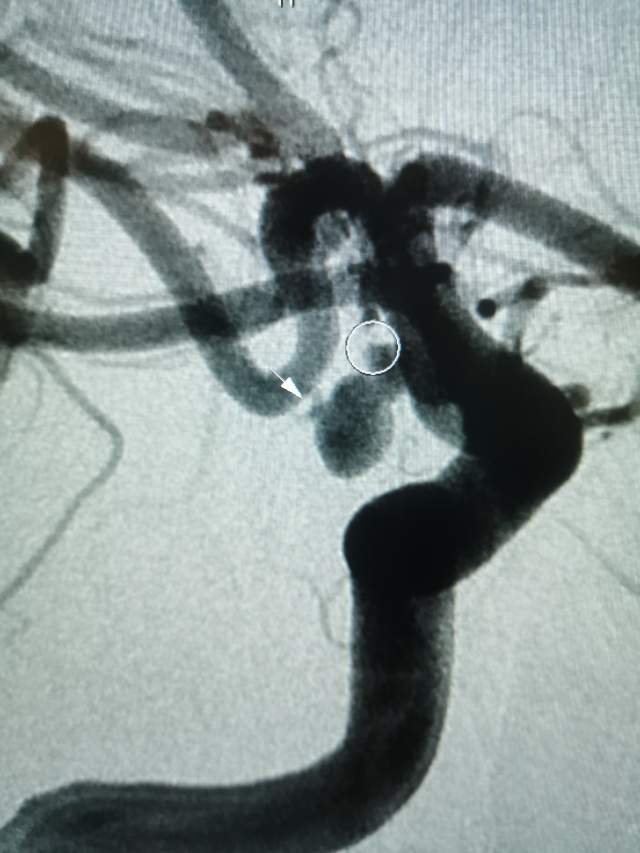

午夜,54岁中年女性,颅内多发动脉瘤破裂出血 ,一个左侧A1动脉瘤,一个左侧胚胎型大脑后动脉瘤(责任动脉瘤;起始部和远端上壁各见一个小泡,后面这个为破裂点;起始部累及粗大胚胎型大脑后动脉),

急诊绿色通道给予责任动脉瘤栓塞,远端破裂小泡完全不显影,近端瘤颈处小泡也基本不显影,胚胎性大脑后动脉保留良好。